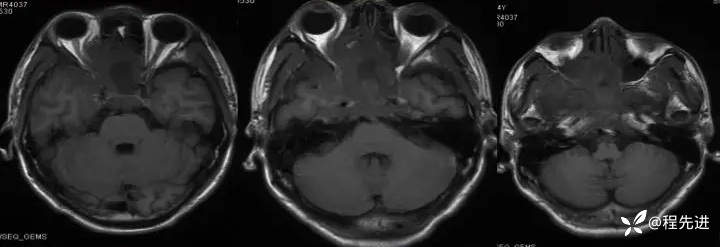

增强:

img